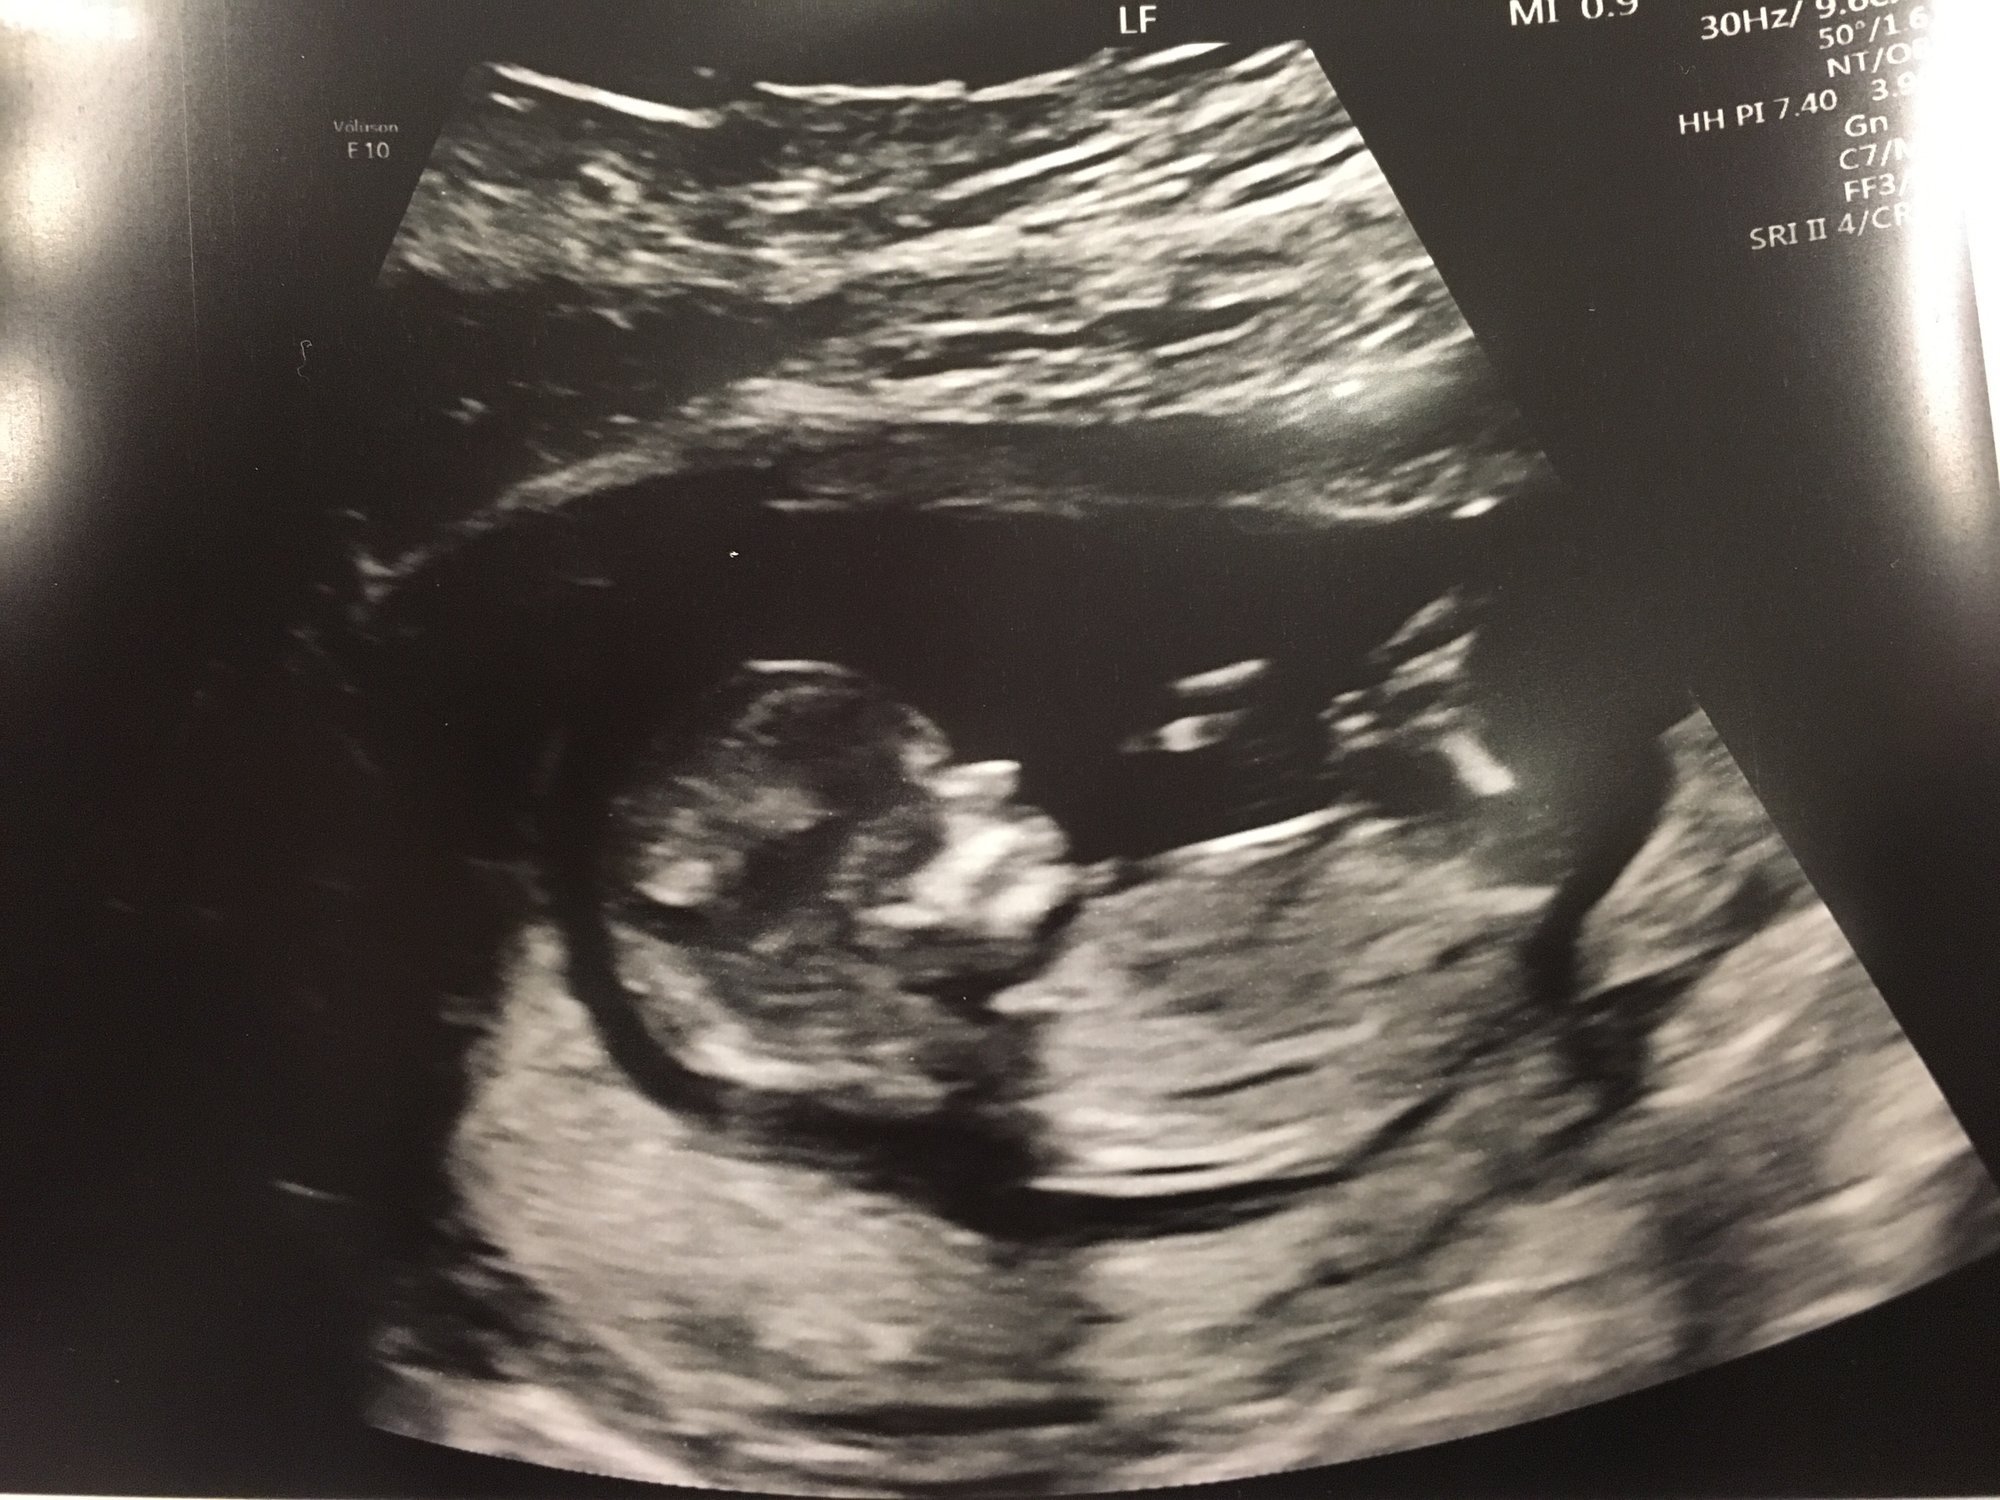

NT scan today. Not the clearest image. Everything looks good! HR was 165 bpm. DS was 164 bpm at this time. Hmmmm!

Vitals: 156–159 bpm, 65mm, 1.6mm translucency.

Heart rate - 172!